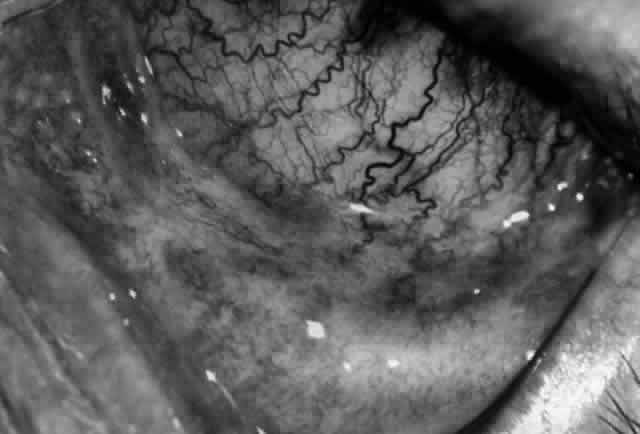

Clinically, the ocular disease in cicatricial pemphigoid (OCP) may present unilaterally in the form of a chronic, recurrent catarrhal conjunctivitis, but it eventually becomes bilateral. Subepithelial fibrosis is characteristic of stage 1 of OCP (Fig. 7). Stage 2 shows fornix foreshortening (Fig. 8), and symblepharon formation is the hallmark of stage 3 (Fig. 9). Stage 4, end-stage disease, is characterized by ankyloblepharon and surface keratinization (Fig. 10). Obstruction of the lacrimal ductules and meibomian gland ducts eventually produces an unstable tear film and progressive sicca syndrome, but it is to be emphasized that OCP is not a dry-eye syndrome until late in the disease course.20 Trichiasis and entropion occur because of the subepithelial fibrosis, with eventual keratopathy, corneal neovascularization, and corneal ulceration and scarring.20

In a series reported from the Mayo Clinic, 21 of 81 patients with cicatricial pemphigoid were blind at the time of the report; 17 of these patients were blind in both eyes. Sixty-two of the 81 patients had ocular involvement; approximately 88% of the 62 patients had the ocular disease bilaterally.18